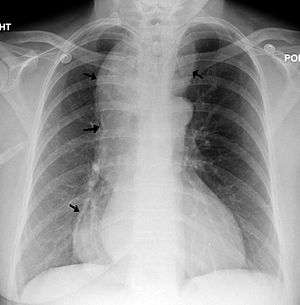

A chest X-ray showing achalasia ( arrows point to the outline of the massively dilated esophagus ) | |